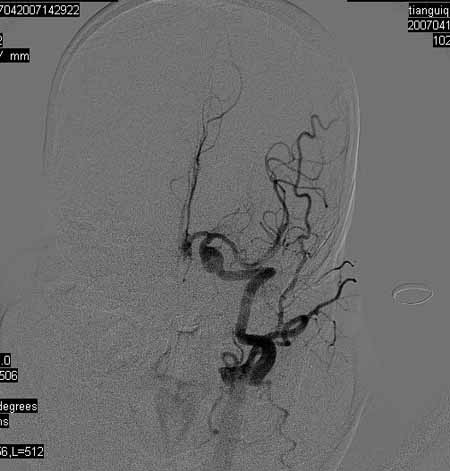

标题: DSA0093:脑血管造影

女,63岁,左侧额、枕叶脑梗塞。

右肾动脉及左颈内动脉起始部狭窄(考虑动脉硬化引起的),大脑中动脉分支减少.